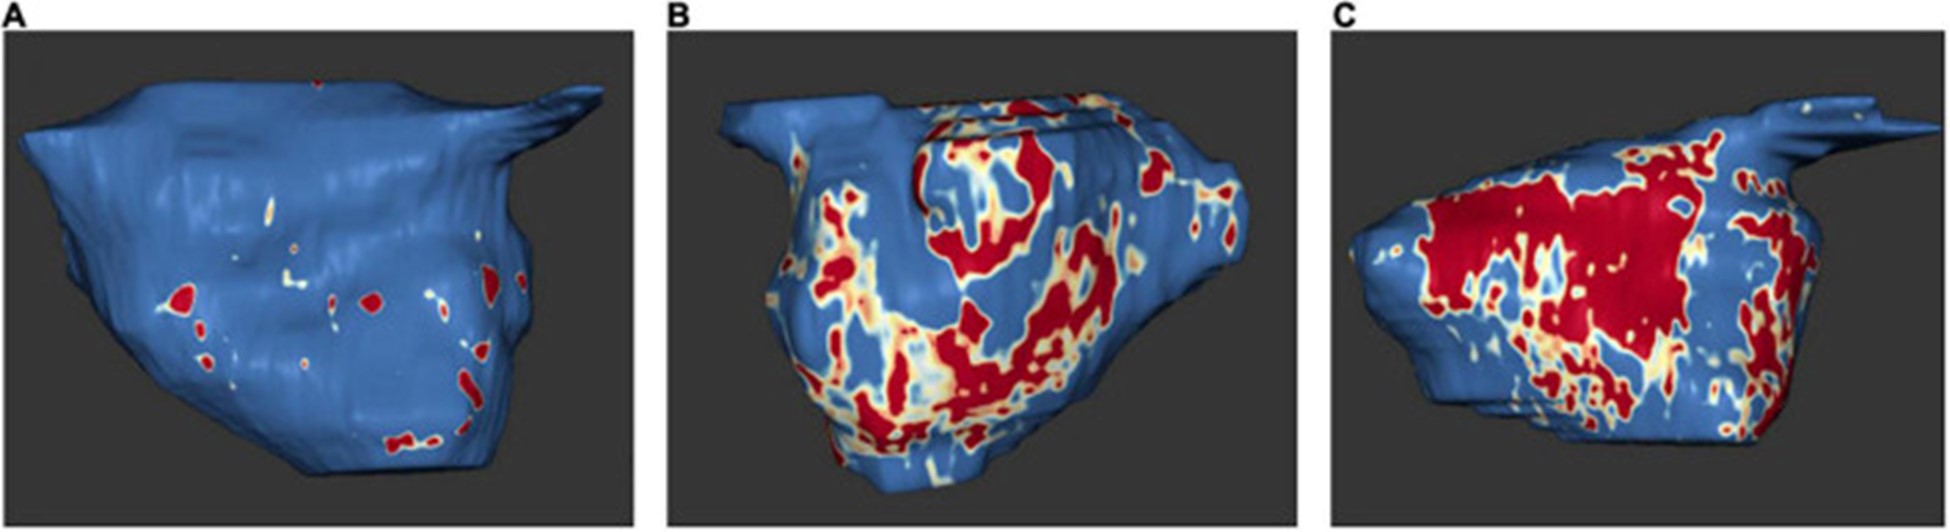

延迟增强磁共振成像

近年来,延迟增强MRI成为检测心房纤维化的关键方法。旨在通过病理延迟增强 MRI 定义左心房心肌病的研究特别关注临床定义(例如 AF、缺血性卒中、主要不良心血管事件)以及进一步的影像学定义(例如异常超声心动图参数、电解剖标测中的低电压区域) (表格1)。

2009 年,Oakes 等人。建立了犹他阶段模型来量化 LA 纤维化 。根据该模型,将严重程度分为四个级别:犹他州 I,定义为 ≤ 5% LA 壁增强,犹他州 II,5–20%,犹他州 III,20–35%,犹他州 IV,>35% (图 5)。

图 5:左心房 MRI 检查示例:基于 3D 延迟增强磁共振成像扫描的左心房组织纤维化。正常左心房壁以蓝色显示,纤维化改变以红色和白色显示。纤维化量占左心房壁总体积的百分比。(A)犹他州第一阶段 (1%)。(B)犹他州第 3 阶段 (27%)。(C)犹他州第 4 阶段 (36%)。在 Misagh Piran 博士(Herz- und Diabeteszentrum Nordrhein-Westfalen,Ruhr-Universität Bochum)的友好支持下。

延迟增强 MRI 与来自 LA 结构重塑的手术活检组织学之间发现了高度相关性,包括间质和脂肪纤维化以及总纤维化和脂肪 。原生 T1 对应于 MRI 和组织学的纤维化程度 。此外,与没有 AF 的患者相比,AF 患者的 LA 壁增强似乎更大(77)。

延迟增强 MRI 发现的 LA 瘢痕区域与心内膜标测中的低电压区域有关 。

由于 LA 晚期钆增强与 LA 射血分数和超声心动图左室间隔 e' 和室间隔 E/e' 之间存在显着相关性,因此更高量的 LA 晚期钆增强与 LA 功能下降以及 LV 舒张功能下降有关(79)。斑点追踪超声心动图也证明了延迟增强和 LA 功能降低之间的相关性。延迟增强 MRI 测量的 LA 壁纤维化程度与斑点追踪超声心动图显示的 LA 应变和应变率之间存在反比效应,特别是 LA 中外侧应变和应变率(80)。有趣的是,与阵发性 AF 患者相比,持续性 AF 患者出现更多的纤维化和更少的中间隔和中外侧应变 。一般来说,新发房性心律失常的风险随着 LA 晚期钆增强量的增加而增加 。

既往卒中患者和卒中高危患者(表现为 CHA2DS2-VASc 评分高)在延迟增强 MRI 中 LA 纤维化的比例显着增加。LA 纤维化是脑血管事件的独立预测因子,显着提高了 CHA2DS2-VASc 评分的预测能力 。上升的犹他阶段和更强烈的 LA 晚期钆增强与主要心血管事件的风险增加有关,主要是由于中风或 TIA 的风险增加(82)。有趣的是,与 AF 患者相比,ESUS 患者的心房纤维化程度相似,这支持了纤维化是缺血性卒中和左心房心肌病的主要危险因素的假设(83)。

通过延迟增强 MRI 测量的结构性 LA 重塑程度似乎与 AF 类型(孤立性 AF 或非孤立性 AF)无关(84)。已证明 AF 消融后的结果显着取决于结构性 LA 重塑的程度,在犹他州分期增加时结果更差 。随着延迟增强水平的增加,消融后 AF 复发的发生频率更高(75)。因此,通过延迟增强 MRI 进行的消融前 LA 纤维化评估可以预测结果 。另一项研究 LA 纤维化对 AF 消融后结果的影响的研究表明,延迟增强 MRI 检测到的 LA 纤维化等级较高时,复发性心律失常的风险出现。77 )。较高的 LA 纤维化等级的存在也是成功消融的最佳预测指标,而增加的 LA 体积和持续性 AF 没有预测作用 。

DECAAF 研究评估了延迟增强 MRI 测量的 LA 纤维化对 AF 消融后结果的影响 。在接受 AF 消融的 329 名患者中,延迟增强 MRI 估计的 LA 纤维化程度与心律失常复发显着相关 。前瞻性、随机、多中心 DECAAF II 研究进一步深入了解通过延迟增强 MRI 对经历 AF 消融的持续性 AF 患者进行术前 LA 纤维化评估的价值 。在 2021 年 ESC 大会上公布但尚未发表的结果表明,纤维化引导消融在减少 AF 复发方面并不优于传统 PVI 。